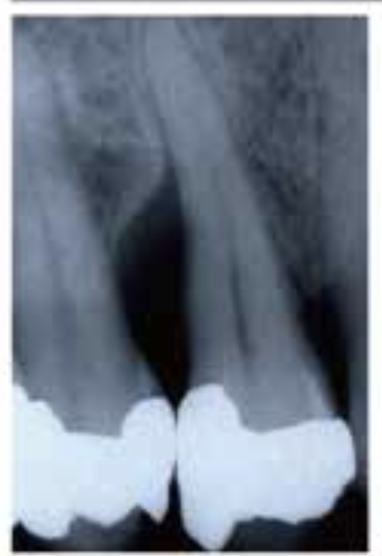

🦷 X-ray 비교

BEFORE

AFTERX-ray 상으로 명확하게 보이는 뼈 재생 효과

1Patient 1: 8년 장기 추적 케이스

치료 시작 전 상태

뼈 재생 진행 확인

재생된 뼈의 장기 유지 확인

✨ 핵심 포인트: Emdogain 치료 후 3년에 걸쳐 점진적으로 재생된 치조골이 8년이 지난 후에도 안정적으로 유지되고 있음을 확인할 수 있습니다. 이는 Emdogain의 장기적인 효과와 안정성을 보여주는 중요한 임상 증거입니다.